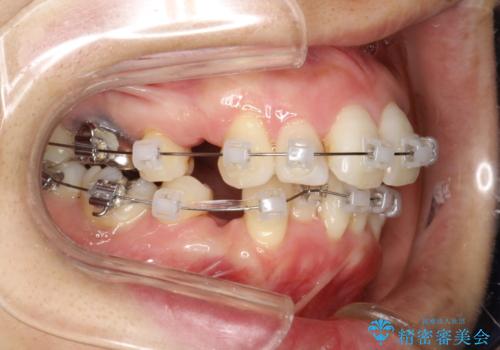

重度のガタガタと出っ歯をワイヤーによる抜歯矯正で整った歯並びへ

- 全体的ながたがたを主訴に来院されました。

上顎の前歯は前方に傾斜して、下顎の前歯は強いガタガタが見られました。

前から4番目の歯を上下左右合計2本抜歯して、歯並びを整える計画としました。

ワイヤー矯正にて治療しました。